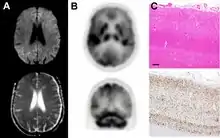

Imaging of the brain may be performed during medical evaluation, both to rule out other causes and to obtain supportive evidence for diagnosis. Imaging findings are variable in their appearance, and also variable in sensitivity and specificity.[43] While imaging plays a lesser role in diagnosis of CJD,[44] characteristic findings on brain MRI in some cases may precede onset of clinical manifestations.[45]

Brain MRI is the most useful imaging modality for changes related to CJD. Of the MRI sequences, diffuse-weighted imaging sequences are most sensitive.[46] Characteristic findings are as follows:

Brain FDG PET-CT tends to be markedly abnormal, and is increasingly used in the investigation of dementias.

- Patients with CJD will normally have hypometabolism on FDG PET.[50]

Histopathology

Testing of tissue remains the most definitive way of confirming the diagnosis of CJD, although it must be recognized that even biopsy is not always conclusive.[51]

In one-third of people with sporadic CJD, deposits of "prion protein (scrapie)", PrPSc, can be found in the skeletal muscle and/or the spleen.[52] Diagnosis of vCJD can be supported by biopsy of the tonsils, which harbor significant amounts of PrPSc; however, biopsy of brain tissue is the definitive diagnostic test for all other forms of prion disease. Due to its invasiveness, biopsy will not be done if clinical suspicion is sufficiently high or low. A negative biopsy does not rule out CJD, since it may predominate in a specific part of the brain.[53]

The classic histologic appearance is spongiform change in the gray matter: the presence of many round vacuoles from one to 50 micrometers in the neuropil, in all six cortical layers in the cerebral cortex or with diffuse involvement of the cerebellar molecular layer.[54] These vacuoles appear glassy or eosinophilic and may coalesce. Neuronal loss and gliosis are also seen.[55] Plaques of amyloid-like material can be seen in the neocortex in some cases of CJD.[56]